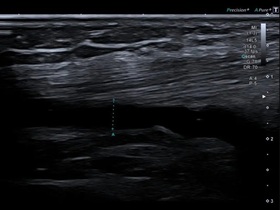

Инструментальная диагностика ревматоидного артрита

- рентгенография;

- артроскопия;

- компьютерная томография;

- магнитно-резонансная томография;

- ультразвуковое исследование суставов.